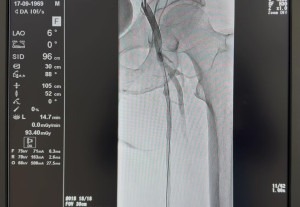

Foto: UKC Tuzla uspostavio redovno izvođenje endovaskularnih procedura perifernog arterijskog sistema

Univerzitetski klinički centar Tuzla nastavlja sa unaprjeđenjem savremenih metoda liječenja u oblasti invazivne kardiologije, započinjući kontinuirano izvođenje endovaskularnih procedura tretmana perifernog arterijskog sistema. Percutaneous Transluminal Angioplasty (PTA) je minimalno invazivna endovaskularna procedura kojom se mehanički proširuje sužena ili okludirana arterija pomoću balon-katetera, a po potrebi se implantira i stent radi održavanja prohodnosti krvnog suda.

Ove intervencije predstavljaju značajan iskorak u zbrinjavanju pacijenata s oboljenjima krvnih sudova, posebno donjih ekstremiteta. Procedura, koja se u UKC Tuzla ranije izvodila intermitentno, izvedena je uz asistenciju kolega iz KBC Zagreb i sada će se kontinuirano primjenjivati u Klinici za invazivnu kardiologiju UKC Tuzla.